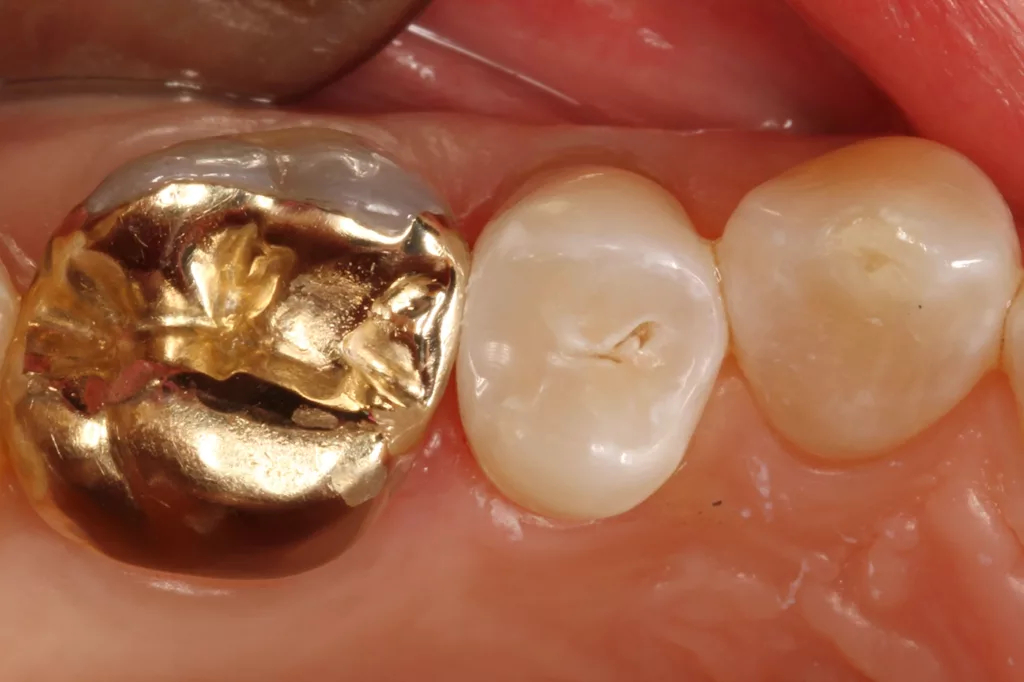

Fall 3: Versorgung einer Initialkaries an Zahn 25 neben einer Goldkrone

Die Versorgung von Approximalläsionen neben Metallfüllungen (Amalgam oder Gold) gestaltet sich bei den gängigen Bulkfill-Materialien daher meist als schwierig, weil aufgrund der hohen Transluzenz der Restaurationsmaterialien die gelegte Füllung oft grau erscheint. Die graue Farbe ist bei klinischen Kontrollen oft schwer zu interpretieren: Es muss eine Kariesausbreitung unter der Füllung klar von der materialintrinsischen Transluzenz differenziert werden.

Aus diesem Grunde ist es sehr zu begrüßen, wenn Bulkfill-Materialien eine Farbanpassung dahingehend aufweisen, sodass sie auf keinen Fall zu transluzent wirken. Dies ist bei den Bulkflow-Materialien Venus Bulkflow ONE, Omnichroma Flow Bulk und Visalys Bulk Flow der Fall. Somit konnte bei der Anwendung des Visalys Bulk Flow in der Kavität neben der Goldteilkrone bei einer hier 57 Jahre alten Patientin ein klinisches Erscheinungsbild etabliert werden, das dem natürlichen Zahn 1:1 entspricht (Abb. 16 bis 19). Das Behandlungsprozedere entspricht den vorangegangenen Approximalfällen. Lediglich anstelle des G-Wedges wurde ein Fusion Wedge (ebenfalls Garrison) eingesetzt, da dieser eine nochmals bessere zervikale Abdichtung der Matrize gewährleistete.